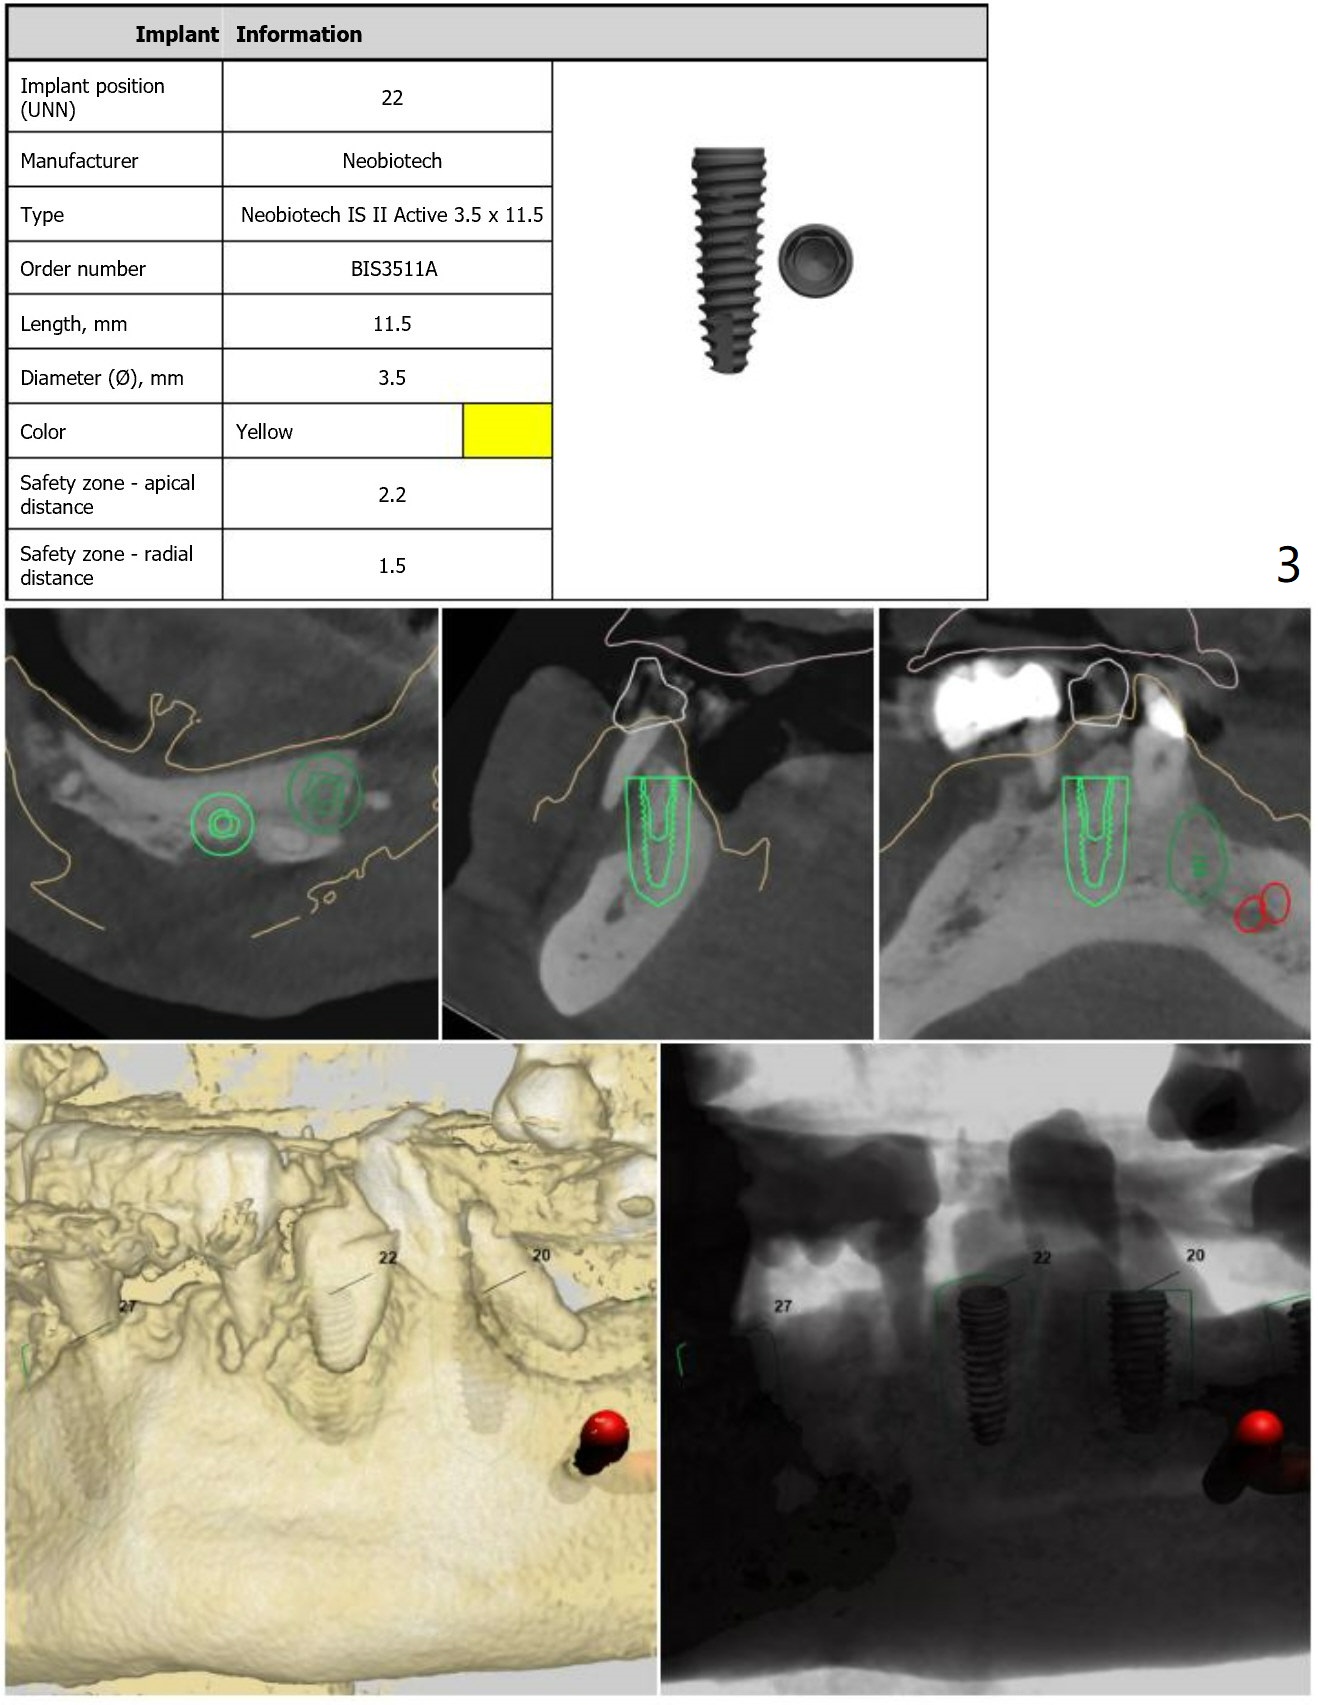

Guide 1 Using the Teeth

#18, 21 and 31 as Anchors

For placement of implants at #20, 22 and 27.